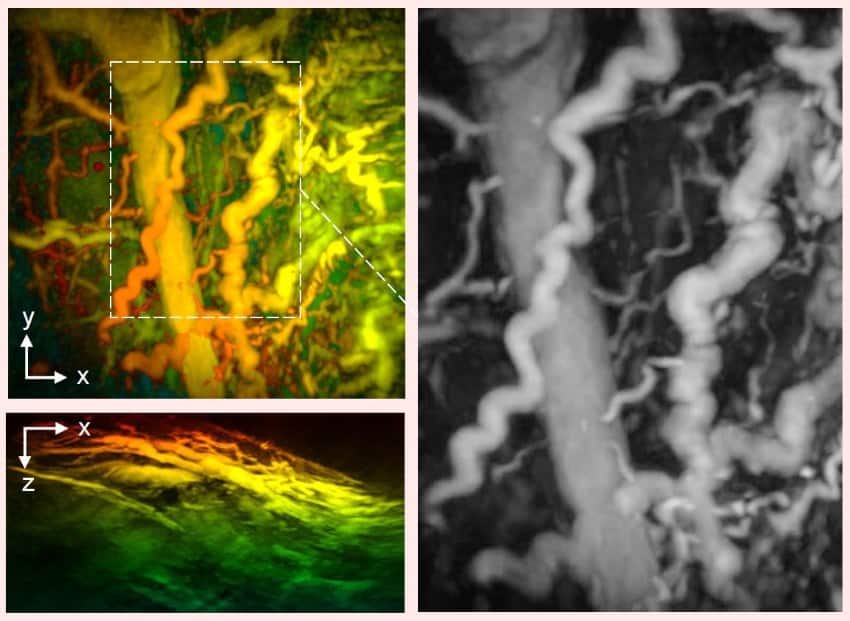

A composite image of 3 scans. The 2 on the left are in yellow, greens, and oranges, and the right image is in black and white. They show 3d images of blood vessels.

Disease captured by UCL hand-held 3D photoacoustic scanner. Credit: Dr Nam Huynh

“In one of our patients, we could see smooth, uniform vessels in the left foot and deformed, squiggly vessels in the same region of the right foot, indicative of problems that may lead to tissue damage in future.